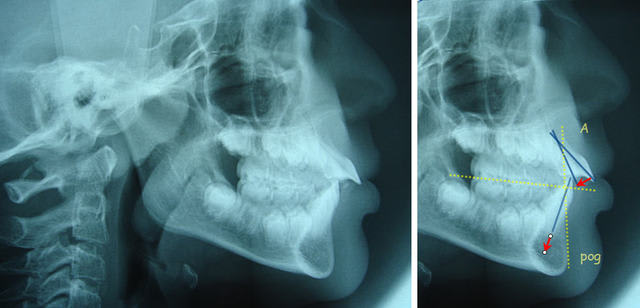

Où vois-tu donc une classe II squelettique avec rétromandibulie ? Les molaires elles-mêmes sont presque en classe I.

Nonobstant leur rotation et leur légère endo, leur position est correcte.

Daniel

P.J. : planche que j'avais déjà envoyée il y a quelques temps.

Pourquoi torquer hyr7u7 - Eugenol